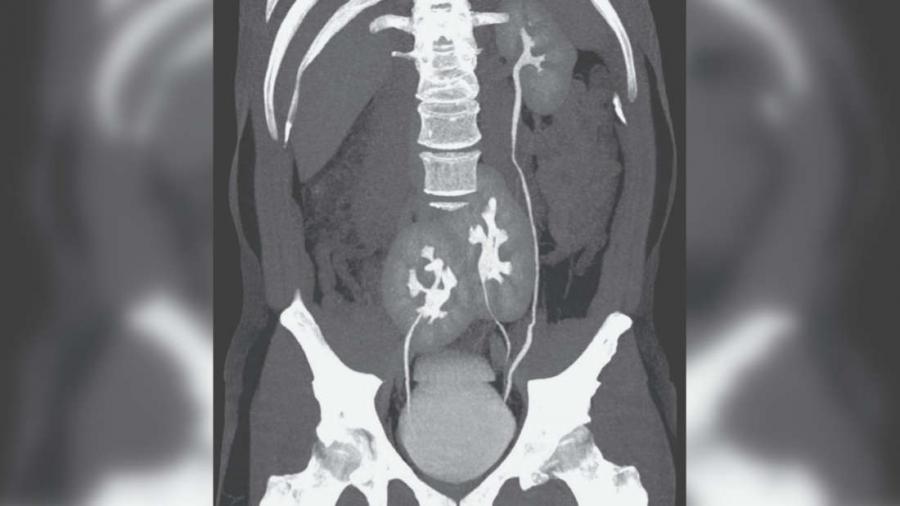

Левият му бъбрек е абсолютно нормален, докато в дясно откриваме два слели се бъбрека.

Уретерът – тръбите в тялото, които пренасят урината от бъбреците към пикочния мехур – от левия бъбрек се свързва с уретера с левия бъбрек от двойката на входа към мехура. Същевременно уретерът на десния бъбрек влиза в мехура от дясната страна.